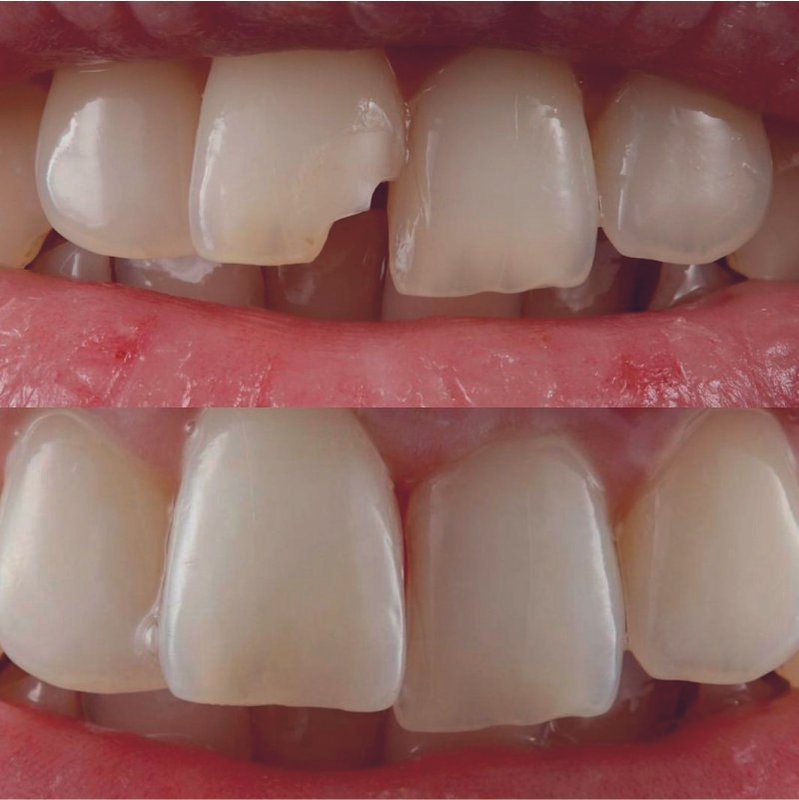

Фотогалерея

Занимается эстетической реабилитацией улыбки путем отбеливания, художественной реставрацией и виниров, а также лечением таких заболеваний, как кариес, пульпит, периодонтит, гингивит, гиперестезия, флюороз и др.